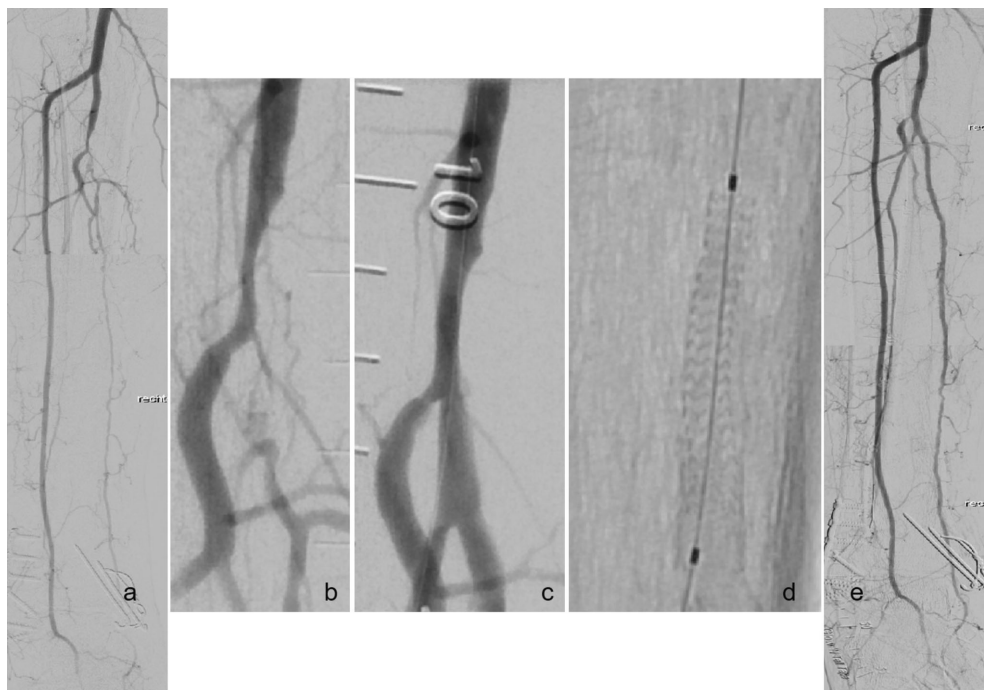

研究人员通过一项前瞻性、单臂、多中心试验,纳入58例Rutherford分级4-5级的CLTI患者,所有受试者均植入MOTIV?支架(材料为Tyrocore?,一种含碘酪氨酸类似物共聚物),并完成36个月随访。主要疗效终点为12个月时的一期通畅率(PPR),安全性终点为30天内无严重器械相关不良事件。次要终点包括技术成功率、24及36个月PPR、临床驱动的靶病变血运重建(CD-TLR)率和肢体挽救率。随访期间通过彩色多普勒超声(CFDU)进行核心实验室裁定评估。

通过核心实验室裁定的CFDU检测发现,12、24和36个月时的一期通畅率分别为88.3%、81.7%和80%。尽管随访肢体数量随时间减少(12个月时43肢,36个月时30肢),但通畅率保持稳定,表明支架在长期内有效维持了血管开放。

30天内严重器械相关不良事件发生率仅为1.7%,技术成功率达99%。仅1例患者术后25天发生闭塞,经PTA和支架处理后恢复。36个月内共4例接受再次干预,但93%的患者免于CD-TLR。

本研究显示,MOTIV?支架在BTK病变中表现优异,其36个月的一期通畅率(80%)和CD-TLR豁免率(93%)均优于既往POBA或BMS的报道(如DESTINY试验中DES组12个月通畅率为85%)。Tyrocore?材料凭借其高径向强度、显影性和均匀降解特性,在抑制内膜增生和支持血管重塑方面展现出独特优势。与同类PLLA支架(如Absorb)或镁合金支架相比,MOTIV?更薄(strut厚度95-115μm)且降解产物炎症反应更低,这可能有助于长期通畅率的维持。